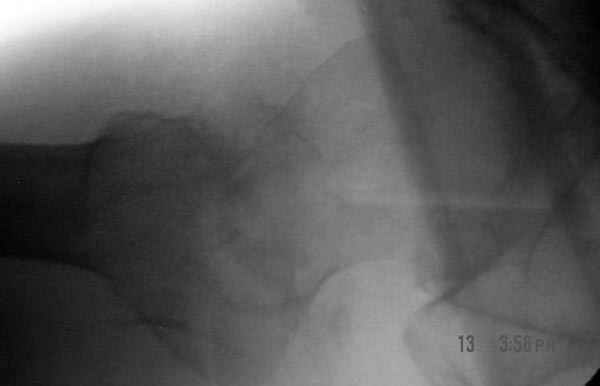

Дорогие коллеги,Как правильно определить такой перелом по классификации AO?

Как два отдельных или есть один соответствующий код? Фиксировать-то оба можно одним фиксатором...

Как раз недавно у меня был примерный случай: больному 36 лет, поступил ночью, травма в результате мотоциклетной аварии, кроме чрезвертельного и спирального перелома левого бедра имеется переломы костей предплечья с этой же стороны. Скелетное вытяжение, а на следующий день больной про оперирован на ортопедическом столе с дистракцией. Чтобы не расколоть чрезвертельный перелом провели временную спицу ближе к переднему кортексу, из малого разреза костодержатель для репозиции, а фиксацию провели антиградным штифтом. Этапы операции на снимках.